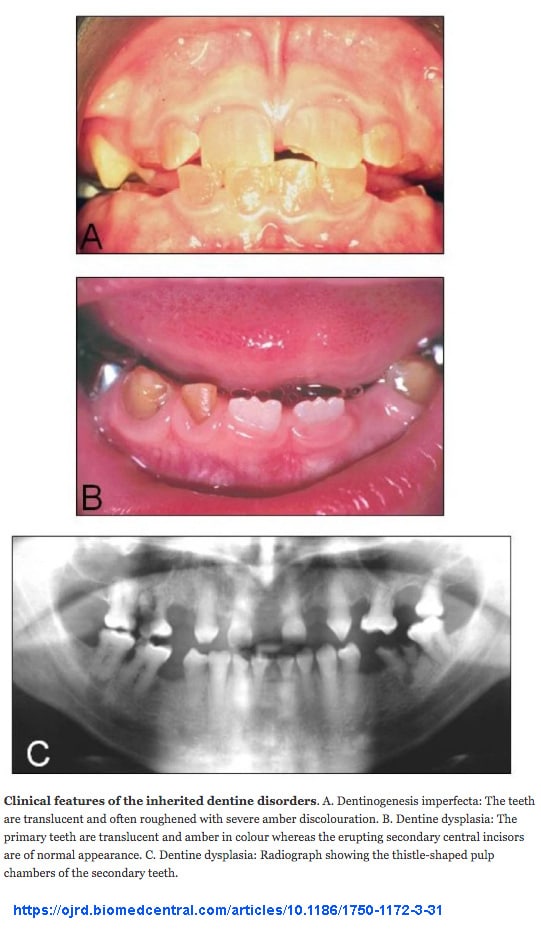

OI Tip III: (Eski adıyla osteogenesis imperfecta congenita, tip Vrolik): COL1A1 veya COL1A2 genlerinden birinde meydana gelen heterozigot mutasyon dan kaynaklanır. Doğum sürecinde sıklıkla çoklu kırıklar meydana gelir. Ergenliğe kadar yaklaşık 100 kemik kırılması gerçekleşir. Fenotip özellikler değişkendir. Tipik olarak son derece kısa boy, ince, kavisli ve yumuşak kemikler, iskelet deformiteleri, skolyoz, dentinogenezis imperfekta ve işitme kaybı ile karakteristiktir. OI Tip III tüm osteogenesis imperfecta vakaların yaklaşık % 5 ni oluşturur. OI Tip III, otozomal dominant modelde kalıtılır. (4)(20)

Hereditary dentine disorders: dentinogenesis imperfecta and dentine dysplasia